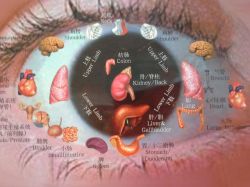

JE TO PŘEDEVŠÍM FAKT, ŽE JAKO LÉKAŘKA S BOHATOU TŘICETILETOU PRAXÍ VIDÍ „VĚCI Z VÍCE STRAN“, její praxe je rozsáhlá jak v medicíně vědecké-západní, tak v tradiční čínské medicíně a „východním přístupu“. Naučíte se, na jakou léčbu si vzhledem ke svému vzdělání můžete troufnout a co raději či ihned přenechat medicíně vědecké. Naučíte se celostnímu pohledu na člověka, v souvislostech moderní i starověké medicíny. Koneckonců takový je i směr současné medicíny čínské, kde lékaři studují medicínu jak západní, tak tu „svoji“. Spojení těchto vícera pohledů na možnosti pacientova léčení je nadějí pro nemocné v novém tisíciletí.

- LÉKAŘI – TI BUDOU MÍT NAVÍC VELMI INTENZIVNÍ VÝUKU AKUPUNKTURY

- MASÉŘI, ZDRAVOTNICKÝ PERSONÁL AJ. – AKUPUNKTURU BUDOU PROBÍRAT V RÁMCI CELKOVÉ ZNALOSTI METOD TAKÉ, ALE PREFERENČNĚ SE BUDOU UČIT METODY NEINVAZIVNÍHO OŠETŘENÍ BODŮ – BAŇKY,KVA-ŠA,MASÁŽ,TUINA, AKUPRESURA, MOXA, SEMÍNKA AJ.